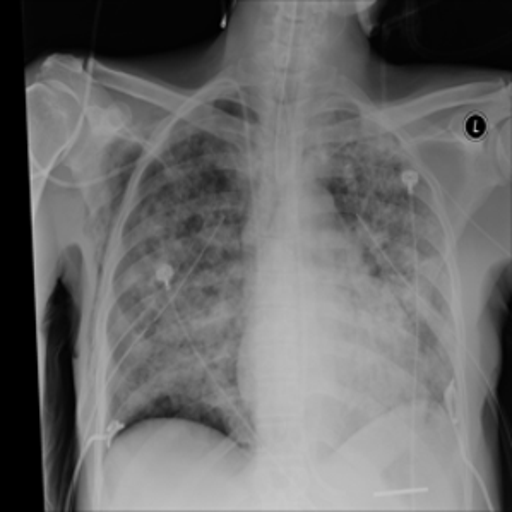

The COVID-19 Radiography Database[45] contains 10192 normal, 3616 COVID-19, 4945 Lung Opacity and 1345 Viral pneumonia chest x-ray images. The dataset is obtained from https://www.kaggle.com/datasets/tawsifurrahman/covid19-radiography-database. The model is fine-tuned on the images using their respective labels as text prompts i.e Normal chest scan, Lung Opacity, Viral Pneumonia, and COVID 19.

4.1 Qualitative Evaluation of Healthy Counterpart Generation

Example images from the disease COVID-19 Radiography Database and their generative healthy counterparts are given in figure 2. The images on the far left are instances of the lung opacity class from the real images in the dataset. The images in the middle column are examples of the generated healthy counterfactuals obtained via latent space diffusion, with RadBERT-guided textual-conditioning via a conditional prompt “normal chest x-ray”. A total of 75 diffusion inference steps are used with image conditioning strength=0.85 and guidance scale=7.5. (The former indicates the level of constraint on changes to the original input image and the latter is the weight given to the textual encoder conditioning in the generation of the image, ranging over [0,1] and [0,9], respectively).

Side-by-side inspection of the generated healthy counterfactuals (as per fig. 2) suggests that, as required, only minimal perturbation is made to the original image with respect to healthy pixels -i.e. localized image sites without structural medical defects. (In the top row, the medical structural defect in the original image is due to a lung opacity, and characterized via a relatively complex interaction between the imaging modality and subject manifesting as ‘gaps’ in the corresponding portions of the lung scan). The healthy/non-healthy discrepancy maps in all of these cases are obtained via masked subtraction of the original image from the generated image (the ground truth segmentation masks correspond to the broad area of interest –i.e. the complete lung). The generated healthy tissue is thus a subset of the mask and is shown in the final column of fig. 2 for the respective cases.

In the context of a VANT-GAN[20]-based approach, this highlighted material constitutes the diagnostic counterfactual visual attribution, i.e. the selection of material relevant to the diagnosis of the unhealthy condition. Healthy counterfactual generation was performed for the complete datasets in the three unhealthy classes, i.e Lung opacity, Viral Pneumonia and COVID, examples of which are given in fig. 3 for the three classes (all of the generated healthy counterfactuals from this experiment can be found on https://huggingface.co/ammaradeel/diffusionVA). Visual inspection indicates that the generated counterfactuals are, in general, visually plausible with minimal perturbation made to the unhealthy image overall. Moreover, the healthy counterpart generation does not appear to unnecessarily affect aspects of the images unrelated to the medical condition, the model selectively making changes to the unhealthy regions in a structurally plausible manner, e.g. generating missing portions of the lung without generating extraneous lung material where it would be expected to normally exist (e.g. in the abdominal cavity).